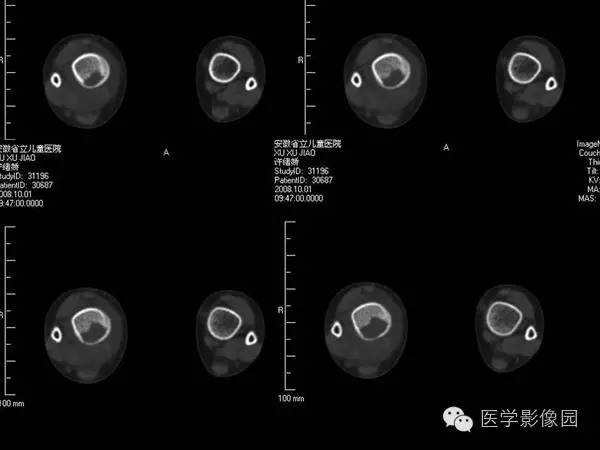

【病例】浆细胞性骨髓炎1例X线及CT影像表现